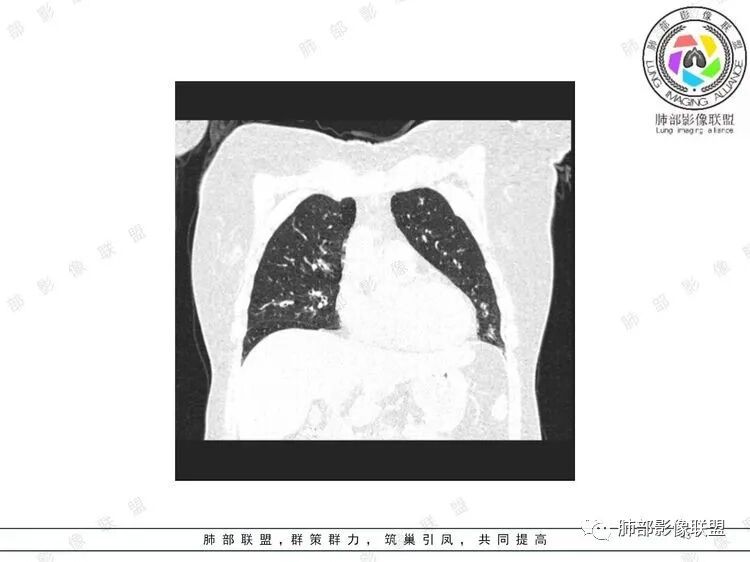

胸CT:双中下肺支气管壁明显增厚,双下肺胸膜下可见实变区。部分病变呈楔形影。

双肺支气管管壁弥漫性增厚,管腔狭窄,下叶为主,伴多发高密度结节影,边缘模糊,双肺支气管血管束明显增粗,临床症状咳嗽低热,有血尿,首先考虑血管炎

影像上:多发结节沿血管分布;双下叶支气管血管束简直增厚,偏血管,支气管通畅

因为支气管壁增厚,远端应该小气道病变,这个不是,反而是血管增粗明显

加上结节的分布,支持血管相关病变